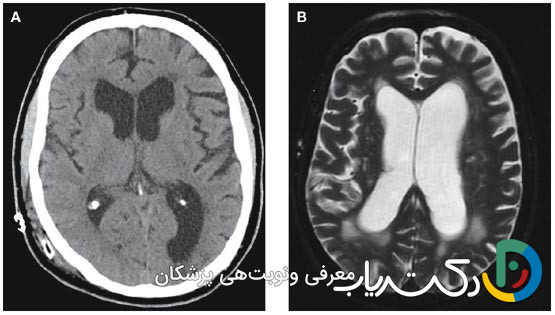

• تشخیص قطعی: تشخیص دقیق یک فرآیند چندمرحله‌ای است که با معاینه کامل عصبی آغاز شده و با روش‌های تصویربرداری پیشرفته مغز مانند MRI (استاندارد طلایی برای مشاهده جزئیات) و CT اسکن (برای ارزیابی سریع و اورژانسی) تأیید می‌شود.

• اسکن توموگرافی کامپیوتری: سی‌تی اسکن با استفاده از اشعه ایکس، تصاویر مقطعی و سریع از مغز ایجاد می‌کند. این روش برای تشخیص‌های اورژانسی (مانند پس از یک آسیب شدید به سر) یا برای ارزیابی سریع اندازه بطن‌ها بسیار مفید است. سی‌تی اسکن به‌وضوح می‌تواند بزرگ شدن بطن‌ها و وجود خونریزی حاد را نشان دهد.

• تصویربرداری رزونانس مغناطیسی (MRI): ام‌آر‌آی به‌عنوان استاندارد طلایی برای تشخیص و ارزیابی کامل هیدروسفالی شناخته می‌شود. این روش بدون استفاده از اشعه ایکس، با استفاده از امواج رادیویی و یک میدان مغناطیسی قوی، تصاویر بسیار دقیق و با جزئیات بالا از ساختارهای نرم مغز ایجاد می‌کند. MRI نه تنها بزرگ شدن بطن‌ها را با دقت فوق‌العاده نشان می‌دهد، بلکه می‌تواند علت زمینه‌ای مانند تومور، کیست، التهاب یا ناهنجاری‌های ساختاری را نیز شناسایی کند. سکانس‌های خاصی از MRI (مانند CINE-MRI) حتی می‌توانند جریان و سرعت حرکت CSF را در مغز به تصویر بکشند و به تشخیص نوع انسدادی از ارتباطی کمک کنند.